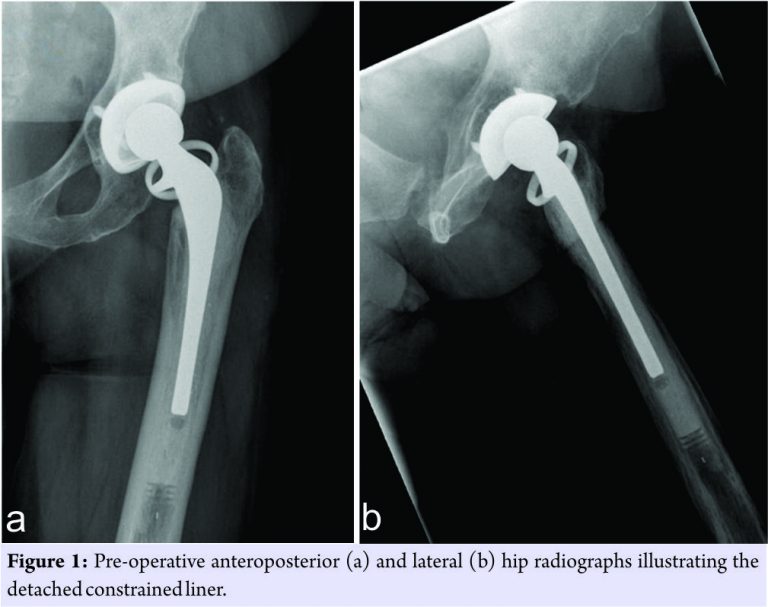

An 84-year-old female patient was seen in the emergency department following a revision total hip dislocation. She had undergone a primary THA in 1999 for avascular necrosis of the femoral head. The primary procedure utilized a hybrid prosthesis, with a cemented femoral stem and uncemented acetabular cup. Her THA functioned well for approximately 15 years until a first revision was required in 2014 for polyethylene wear resulting in hip dislocation. Both stem and cup were left intact during the first revision, with a constrained liner and new femoral head inserted to prevent further dislocation. However, recurrent dislocations were experienced shortly after the first revision surgery. Despite management through closed reduction, pain medication and rehabilitation, the patient was seen in the ED following her fifth dislocation in late 2016. The patient presented with a complex medical history, including sickle cell disease, hypothyroidism, and gastroesophageal reflux disease. Before ED admittance, the patient was mobile with the use of a Rollator walker but experienced an antalgic gait and increased walking difficulties. Despite regular Percocet use to control sickle cell crisis symptoms, the patient presented with pain in the left buttock, groin, and posterior aspect of her hip. Following examination in the ED, a second revision surgery was deemed necessary. Here, we report the findings of this second revision procedure. Pre-operative radiographic analysis revealed disengagement and inferior migration of the constrained liner, with suspicion of a fragmented polyethylene liner superolaterally (Fig. 1).

The acetabular cup was noted to be quite vertical but with no evidence of periprosthetic fracture. It was expected that complete removal and replacement of the acetabular cup component would be required, and a surgical plan for the cup revision was prepared. Revision THA was performed through the posterior approach, with the assistance of the Intellijoint HIP® mini-navigation tool (Intellijoint Surgical Inc., Waterloo, ON). The use of the mini-navigation system has been described elsewhere [7]. In brief, the system utilizes a camera, which sits atop a pelvic platform fixed to the ipsilateral iliac crest through two surgical screws. The camera captures the position and movement of a tracker that can be magnetically attached to a small platform fixed to the greater trochanter or to surgical tools (e.g., impactor and surgical probe). The camera relays data regarding the position and movement of the tracker to a workstation, located outside of the surgical field but within view of the surgeon. Installation of the navigation system was completed before dislocation and used to determine the initial leg length and offset. On initial surgical examination, damage to the posterior aspect of the liner due to impingement was noted and substantial bony ingrowth around the acetabular cup component had occurred. After posterior dislocation and removal of the polyethylene liner, the navigation probe and tracker were used to verify a cup position of 45° inclination and 27° anteversion. While more anteverted than desired, the cup was stable and in good condition. The decision was made to preserve the cup component and correct the excessive anteversion using a new cemented constrained liner. After thorough irrigation and roughening of the cup interior, the new liner was cemented in place with slight retroversion relative to the cup. The navigation tool was successfully used to guide liner placement, providing updated measurements on position until a final liner orientation of 45° inclination and 19° anteversion was achieved. The femoral stem was found to be stable, and a femoral head with a longer neck length (+7 mm) was inserted to reduce the chances of levering. No signs of impingement were noted, and navigation confirmed that leg length and offset remained stable. Navigation enabled modification of the initial surgical plan, resulting in successful preservation of the primary acetabular cup and stem (Fig. 2).